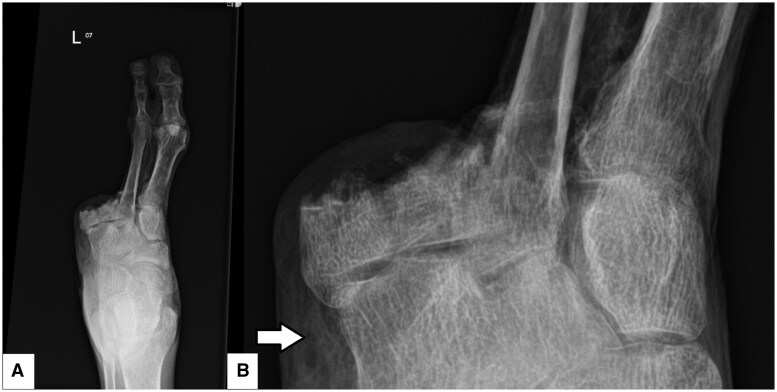

肺气肿性骨髓炎(EO)是一种罕见但严重的骨髓炎,其特征是骨内形成气体。本病例报告强调了一个截肢足的特别严重的EO病例,不同模式的关键影像学发现强调了诊断的挑战和早期发现的重要性。68岁男性,糖尿病控制不佳病史,因溃疡未愈合而截肢左三至第五趾,以感染图片和血糖控制不佳来到急诊科。经临床评估,发现感染病灶位于左脚,随后通过x线平片、MRI和CT进行评估。该病例强调了每种模式在这种复杂表现中的作用,包括平片上的骨小梁改变,MRI上的软组织改变和CT上的骨内肺病的确认。本病例强调了EO的主要影像学特征,并强调了使用CT和MRI及时指导手术和医疗管理的必要性。本报告补充了有限的EO文献,并提出了一个有用的缩写“LEAP”来描述怀疑EO时的关键特征-缺乏皮质破坏,骨外软组织气体,相关合并症(糖尿病,恶性肿瘤等)和浮石征。

Emphysematous osteomyelitis (EO) is an uncommon but severe form of osteomyelitis that is characterized by gas formation within the bone. This case report highlights a case of particularly severe EO in an amputated foot, with key imaging findings across modalities emphasizing the diagnostic challenges and the importance of early detection. A 68-year-old male with a history of poorly controlled diabetes and a previous left third to fifth toe amputation for a non-healing ulcer presented to the emergency department with an infective picture and poorly controlled blood glucose levels. After clinical assessment, a focus of infection was found in the left foot and was subsequently assessed with plain radiography, MRI, and CT. The case highlighted the utility of each modality in such a complex presentation, including trabecular bony changes on the plain radiograph, soft tissue changes on MRI and confirmation of intraosseous pneumatosis on CT. This case highlights key imaging features of EO and underscores the need to use CT and MRI to guide timely surgical and medical management. This report adds to the limited literature on EO and presents a useful acronym of "LEAP" to describe key features when suspecting EO - lack of cortical destruction, extra-osseous soft tissue gas, associated comorbidities (diabetes, malignancy, etc), and pumice stone sign.